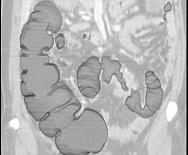

问题 女,56岁,腹胀、腹痛、左下腹包块三月余,无肛门排气,影像检查如图,最可能的诊断是 ( )

选项 A.乙状结肠Crohn病 B.乙状结肠结核 C.乙状结肠腺癌 D.乙状结肠淋巴瘤 E.乙状结肠息肉

答案 C